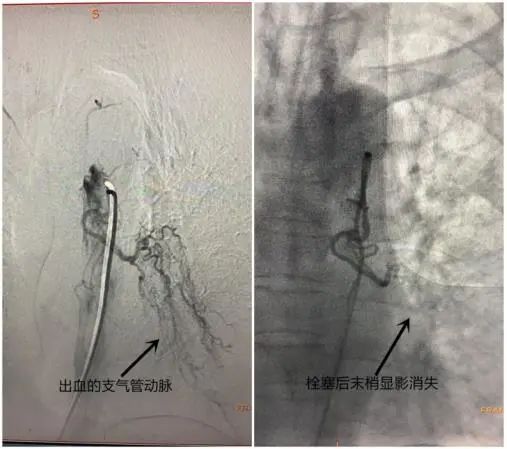

9月4日中午13:00左右,井冈山大学附属医院介入血管外科值班医生接到电话,吉州区一62岁的危重症大咯血(约500毫升)病人马上就要来院救治,凝血血块堵塞气道,出现窒息缺氧的紧急状况。救护车迅速将其转运到附属医院,医院副院长、介入血管外科专家黄玲博士立即组织抢救,启动绿色急救通道,将病人护送至重症医学科(ICU),做了气管插管保证呼吸道通畅。与此同时,介入、麻醉团队迅速到位,13:50为患者做急诊微创止血手术——气道保护下介入支气管动脉栓塞止血术。3:30左右,手术顺利结束,患者停止咯血,送回病房进行后续的治疗。现在,病人的病情持续好转,没有再出现大的咯血。